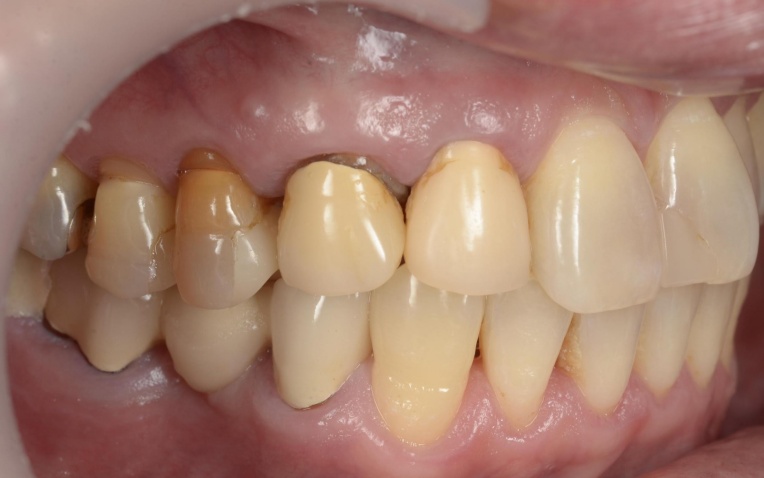

拝見したところ、右下奥歯(第2大臼歯)が折れていることが確認できました。

この歯は、過去に神経を取る治療を受けています。

また、患者様は下顎が上顎よりも前に出る「反対咬合(こうごう)」、いわゆる受け口の傾向があることがわかりました。

このような骨格の特徴がある場合、噛む力のバランスが崩れやすく、奥歯や前歯に負担がかかりやすくなります。

さらに、神経を取った歯は歯がもろくなりやすく、強い力がかかり続けると歯が折れるリスクが高まります。

今回折れてしまったのも、噛み合わせが影響していると考えられました。

治療前